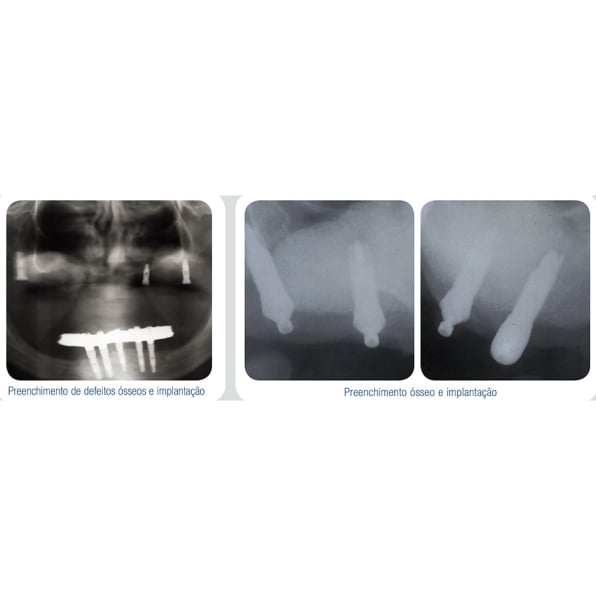

Os produtos OSTEOSYNT vêm sendo cada vez mais utilizados na Implantodontia, nos procedimentos de reconstrução do rebordo alveolar total ou parcialmente perdido, como conseqüência de doenças periodontais, cistos, tumores, traumatismos e consequente perda de elementos e necessidade de sua substituição.

Veja abaixo alguns casos já tratados com as biossoluções EincoBio com resultados de sucesso:

- Aumento de rebordo vertical e horizontal;